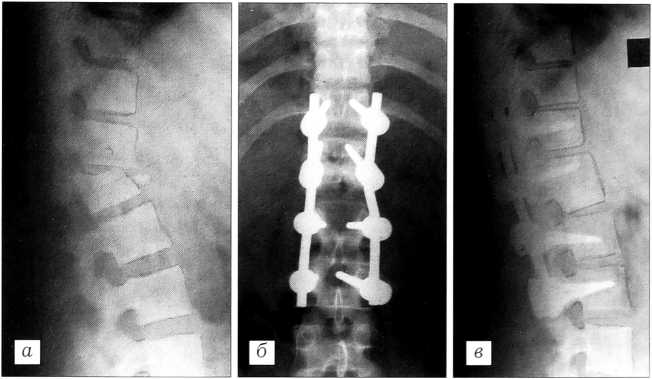

Больная П.,13 лет, поступила через 6 мес после травмы — осложненного переломовывиха L1 позвонка. 12.09.98 произведены корригирующая вертебротомия T12-L1 позвонков с транспедикулярной фиксацией винтостержневой системой типа «Diapason», менингомиелорадикулолиз. Достигнута полная коррекция деформации позвоночника (рис. 4).

Рис. 4. Спондилограммы больной П. до операции (а), после операции (б) и в отдаленный срок (в).